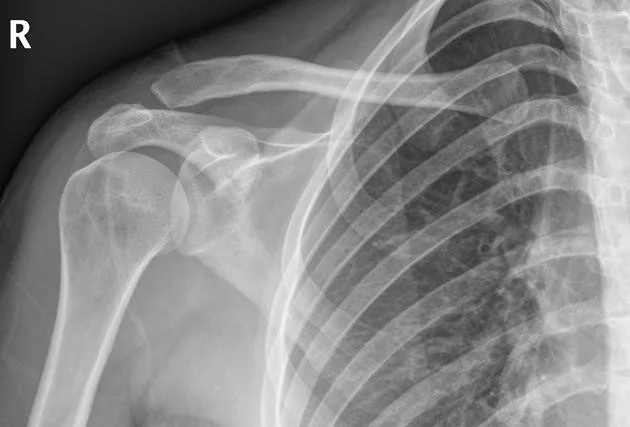

A 19 year-old male presents to the emergency department with a complaint of right shoulder pain. He was tackled from behind in a rugby game three days prior to presentation and has been experiencing pain over the anterior aspect of his right shoulder since that time. Physical exam is notable for tenderness over the right acromioclavicular (AC) joint and pain with both active and passive range of motion of the right shoulder. X-rays (Figure 1) show “no obvious fracture or subluxation.” However, based on your exam and clinical suspicion, closer inspection reveals abnormal alignment between the clavicle and the acromion consistent with AC joint injury.

Figure 1

Figure 1: Case courtesy of Dr Henry Knipe, <a href="https://radiopaedia.org/">Radiopaedia.org</a>. From the case <a href="https://radiopaedia.org/cases/30774">rID: 30774</a>